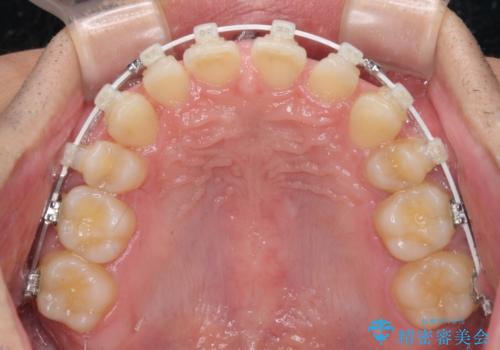

- 矯正装置

- 審美装置

アンカースクリューを用いて下に位置している上顎前歯を持ち上げるとともに、ワイヤー装置によりディープバイトの原因である奥歯の傾斜を改善することで、矯正治療を行っていくこととしました。

顕著なディープバイトのため、頻繁に装置が脱離することがあり、治療期間が想定よりも長くかかることがありますが、当初の予定期間で無事に治療を終えることができました。